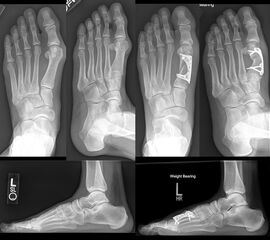

Zum Lesen der Bildbeschreibung und zur Vollansicht bitte das Bild anklicken. Bild: Amol Saxena.

Diaphysäre Osteotomien können mit einer Akin-Osteotomie kombiniert werden, zur gleichzeitigen Korrektur eines Hallux valgus interphalangeus und zur Zentrierung der Strecksehne über dem Drehpunkt des Großzehengrundgelenks.

Zum Lesen der Bildbeschreibung und zur Vollansicht bitte das Bild anklicken. Bild: Markus Walther.